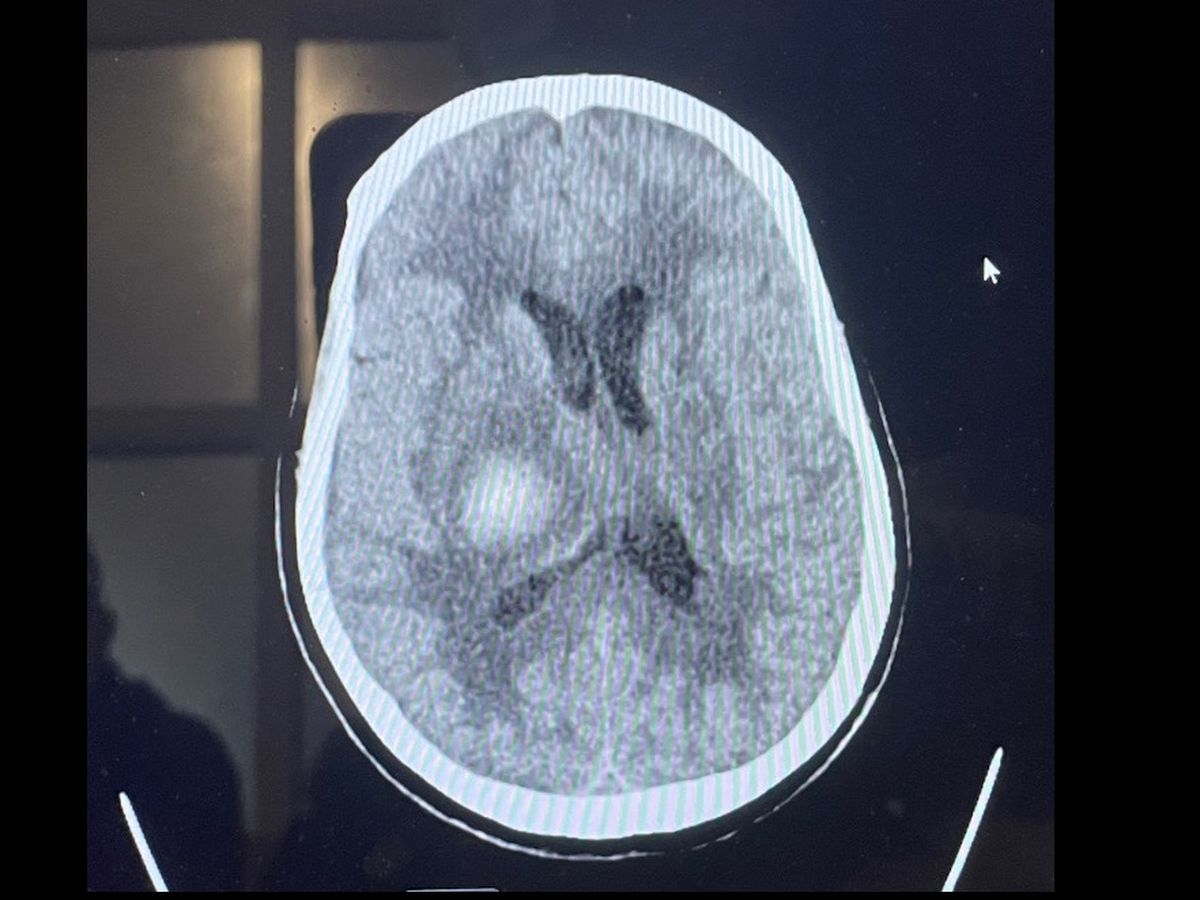

Adela Rodriguez Deras suffered from a stroke on Thursday February 3rd, 2022. After 28 days of slow and steady progress as well as preparation to leave the ICU and move into an acute care facility where there was hope for her to gain the strength to come home, she suffered from another severe stoke. Adela fell into a coma at 3:33 am on Thursday March 3rd, 2022. The amount of pressure in her cranium was too much for her to bare and left our loving Adela brain dead.